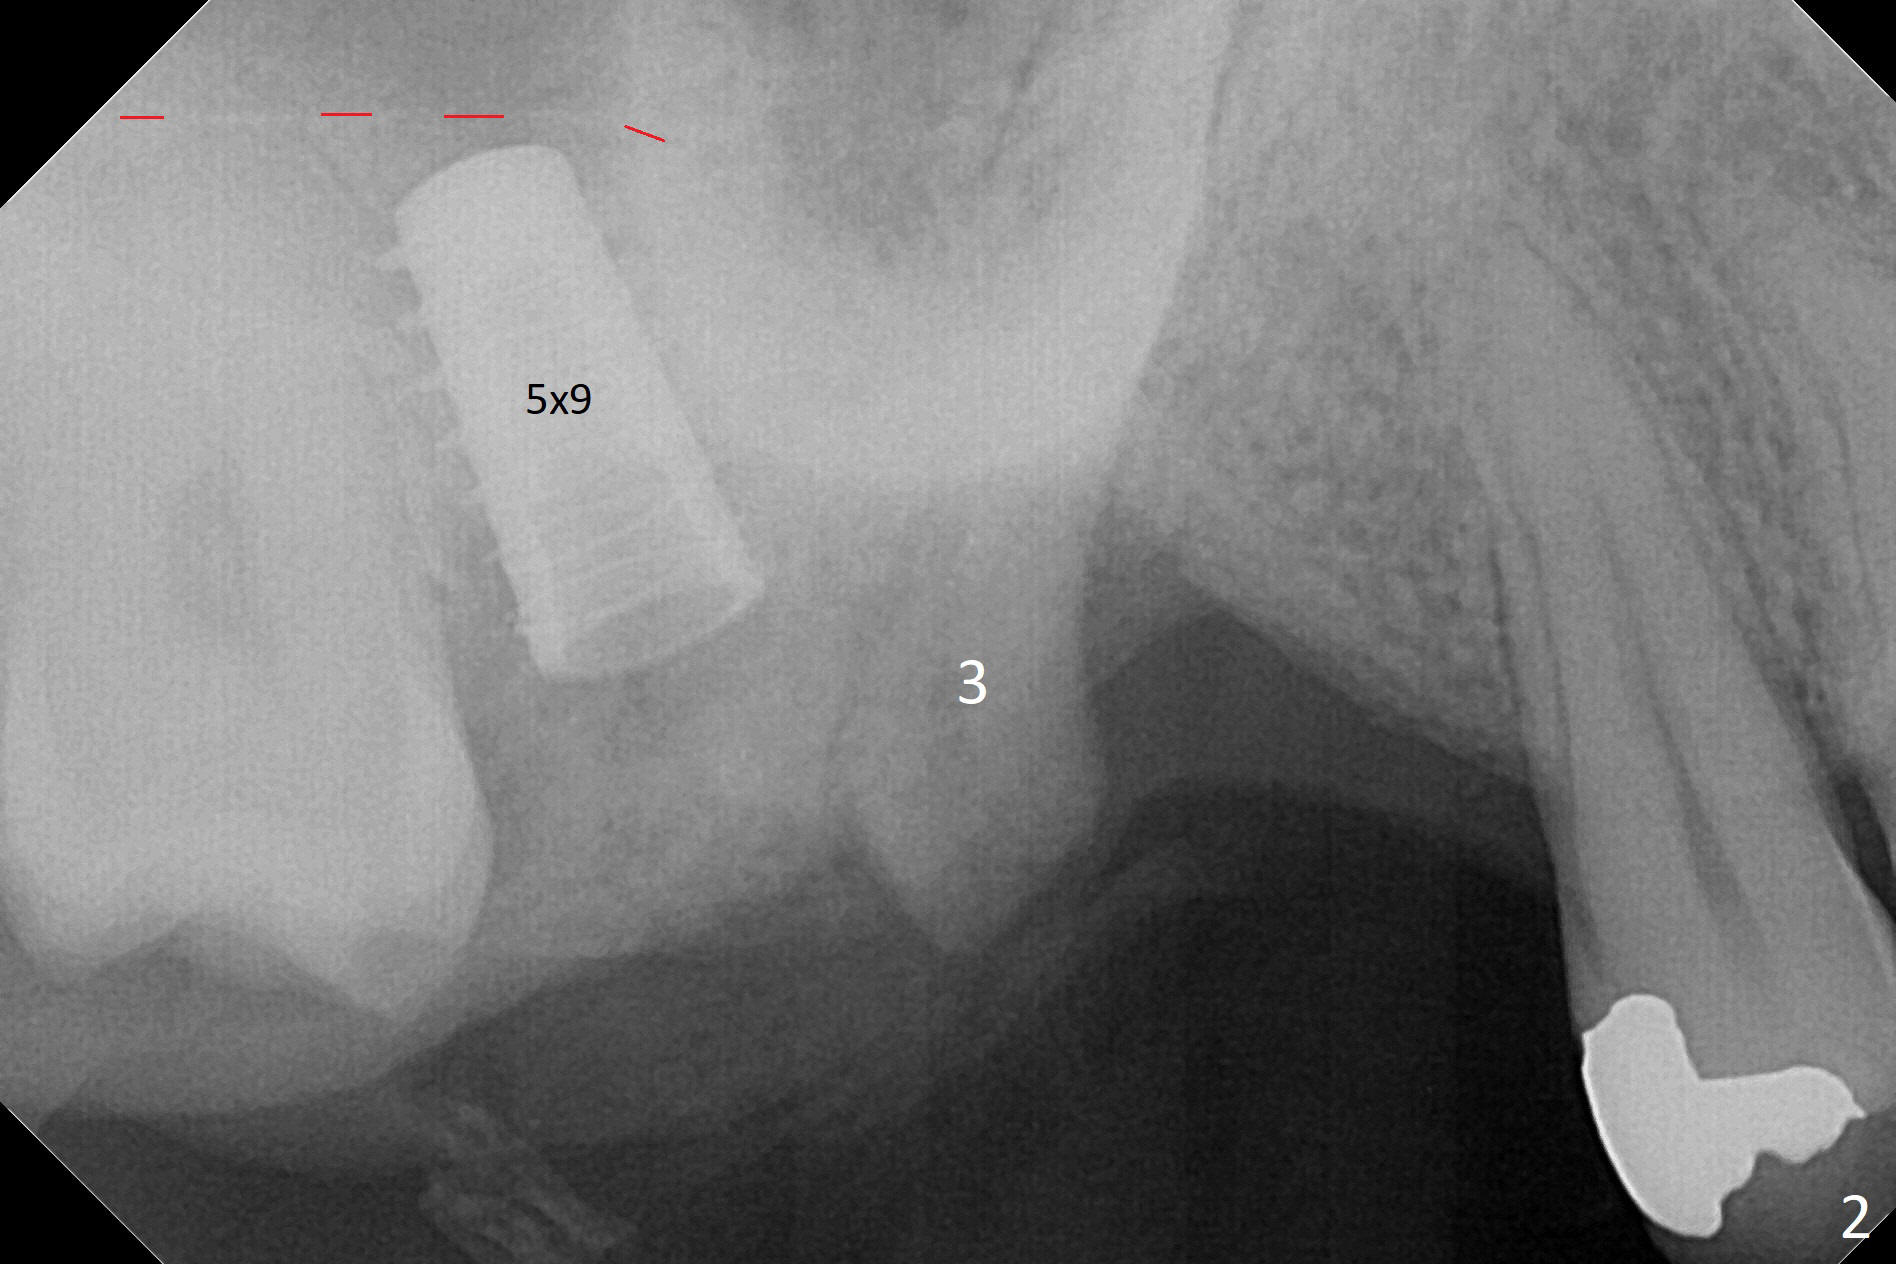

It is difficult to use hard tissue landmark (drill stopper) to make osteotomy in the fresh extraction socket because of socket irregularity and hemorrhage. Once osteotomy is initiated, depth is more reliably controlled with soft tissue landmark (such as gingival margin). This happens in today's case. Without CT information, the osteotomy is established in the buccal slope of the septum of the tooth #2 (after extraction) by using alternatively Magic Sinus Lifter and 4.8 mm Magic Drill (MD). Finally the sinus floor (Fig.1 red dashed line) is lifted after the MD reaches ~16 mm counting from the gingival margin, consistent with preop panoramic X-ray and intraop PA measurement. The 4.5x11 mm dummy implant is close to the impacted 3rd molar (1). Following use of Lindamann bur to move the osteotomy mesially, a 5x9 mm dummy implant is placed away from the 3rd molar (Fig.2 (3: residual root of the 1st molar)). The latter is intentionally not removed in order to maintain osteotomy integrity. A 5x13 mm IBS implant is placed with >50 Ncm; a 6.5x4(4) mm abutment is hand tightened (Fig.3). The remaining large socket is filled with Vera Graft (Fig.4 *). Two months postop, the abutment changes to 6.5x5.7(2) mm without provisional (Fig.5). Nearly 3 months postop, the patient will return for #3 residual root extraction and implant placement with incision (Fig.6). Osteotomy will be initiated in a slope. Prepare surgical round bur for flattening. After placement of a healing abutment, periodontal dressing is to be applied. Take photos to show gingival adaptation to the new abutment without implant exposure at #2.